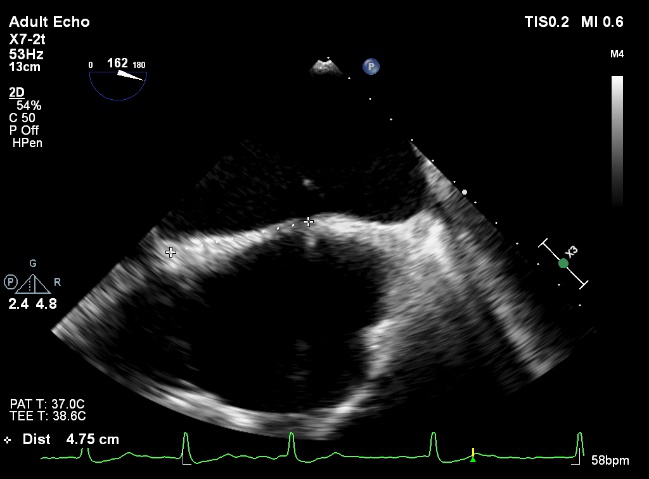

LVOT-color:MR(重度),返流面积11.3cm2

Qlab软件勾画估测瓣口面积约:6.16cm2